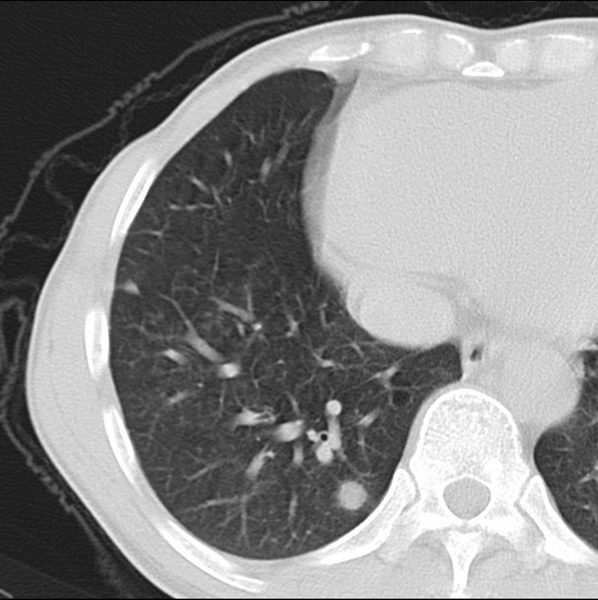

男、48、咳嗽。

胸片示双肺纹理紊乱,行胸部ct检查。

右肺下叶基底段结节影,双肺粟粒样阴影,ct值测量约-20hu左右,可能不准。

层厚层距为4mm左右,病灶轴面最大径约1cm左右。